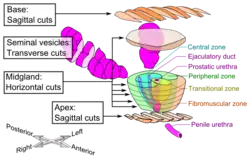

Histopathologic diagnosis of prostate cancer

A histopathologic diagnosis of prostate cancer is the discernment of whether there is a cancer in the prostate, as well as specifying any subdiagnosis of prostate cancer if possible. The histopathologic subdiagnosis of prostate cancer has implications for the possibility and methodology of any subsequent Gleason scoring.[1] The most common histopathological subdiagnosis of prostate cancer is acinar adenocarcinoma, constituting 93% of prostate cancers.[2] The most common form of acinar adenocarcinoma, in turn, is "adenocarcinoma, not otherwise specified", also termed conventional, or usual acinar adenocarcinoma.[3]